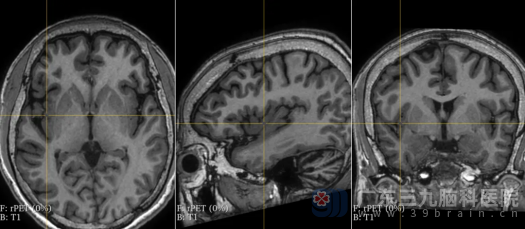

图4

视频脑电图上机2天,提示患者发作间期右侧后头部和前头部有癫痫样放电,无减药诱发发作下共记录到10次,每次发作均有“军帽征”表情(扁嘴、痛苦表情)→床上左右滚动、口中发出无意识“啊啊”声,同步记录心电图课件心率增快(植物神经症状),随后发展为全身抽搐(GTCS),左侧肢体症状为著。MRI检查虽未发现明显异常,但PET检查提示右侧前扣带回、右侧颞-岛叶、右颞底面低代谢(图1~4)。同时,智力测试结果显示,患者的全量表智商(FIQ)为62,言语智商(VIQ)为66,操作智商(PIQ)为62,记忆商数(MQ)低于51,这表明癫痫对他的智力造成了严重影响。